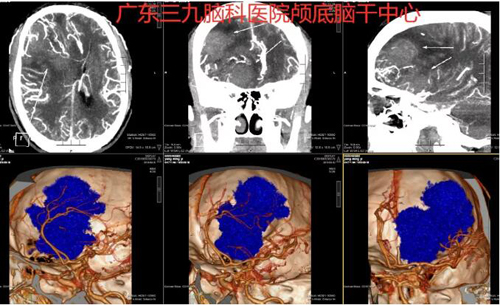

图1:术前CTA示右侧额叶示团块状占位性病变,边界不清,其内示多发异常增粗迂曲血管影,主要供血自右侧大脑中动脉分支,邻近双侧大脑前动脉受压向左侧推移,右侧大脑中动脉受压向后推移;余各脑动脉主干及分支走行僵硬,管壁毛糙,未见狭窄、闭塞、畸形血管及局限性囊状增粗影,左侧大脑前动脉A1段纤细。所见左侧颈内动脉虹吸部管壁示少许斑点状高密度硬化斑块影。